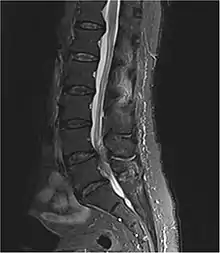

| Diagnostic method | Medical imaging (MRI, CT scan)[1][3] |

Diagnosis is first suspected clinically based on history and physical exam and usually confirmed by an MRI scan or CT scan, depending on availability.[4] Bladder scanning and loss of catheter sensation can also be used to evaluate bladder dysfunction in suspected cases of cauda equina syndrome and can aid diagnosis before MRI scanning. Early surgery in acute onset of severe cases has been reported to be important.[4]